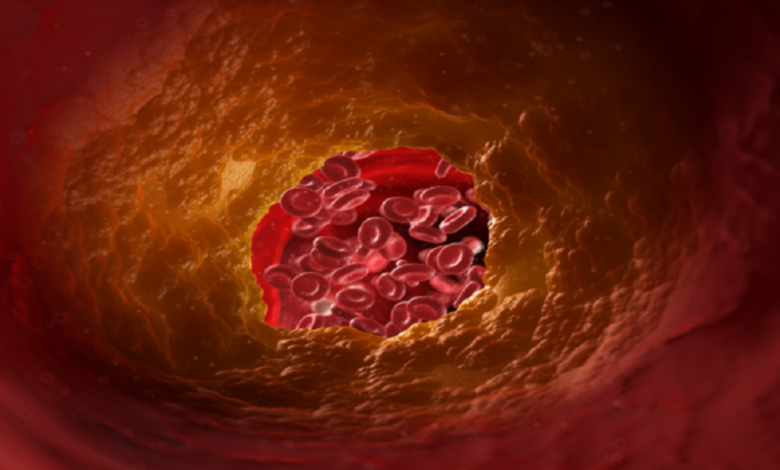

متابعات – عين اليمن الحر يمكن أن يسبب ارتفاع نسبة الكوليسترول في الدم مجموعة متنوعة من المشاكل الصحية الخطيرة.…